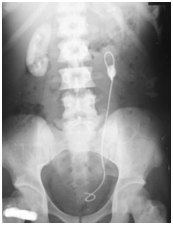

Figure 1 Abdominal X-ray of subject 2, showing a left sided upper ureteric calculus with the stent in situ. Calcified left kidney outline is visible, while the right sided kidney appears radio-opaque due to heavy deposition of calcium oxalate. Note the high density of the bones due to oxalate deposition (bone oxalosis).